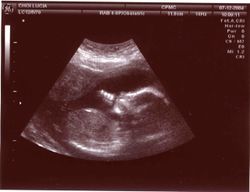

صورة موجات فوق صوتية لجنين داخل الرحم

دخلت الأمواج فوق الصوتية كوسيلة تشخيصية إلى عالم الطب لأول مرة في عام 1942 من قبل العالم Dussik الذي حاول بوساطتها تحديد الأورام الدماغية . وفي عام 1952 استخدم Donald الأمواج فوق الصوتية في بعض القياسات داخل الرحم مثل قياسات رأس الجنين وفحص أعضائه الأخرى وتطور استخدام هذه الأمواج خلال السبعينيات حيث تم استخدام أجهزتها بشكل هائل .

الاستعمالات الخاملة

تتضمن تلك الاستعمالات التي تستخدم فيها الموجات فوق الصوتية في الحصول على المعلومات فقط. على سبيل المثال، يستخدم الأطباء الموجات فوق الصوتية للتأكد من نمو الأجنة0 ويمكن لبعض معدات الموجات فوق الصوتية رسم صورة الجنين على شاشة. كما تساعد هذه المعدات أيضاً في تشخيص الأورام وحصوات المرارة وأمراض القلب، علاوة على بعض الاضطرابات الأخرى. ويعتقد معظم الأطباء أنه لاتوجد آثار جانبية خطيرة للفحوص التي تستخدم فيها الموجات فوق الصوتية.